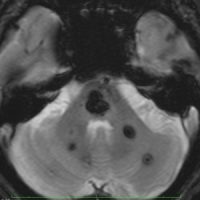

脳幹部の海綿状血管腫 brainstem cavernous hemangioma

2度の延髄内出血を生じた海綿状血管腫です。でも初回の出血からすでに27年間がたちます。症状も回復して麻痺もなくていまは社会生活に困ることはありません。脳幹部の海綿状血管腫の中には1ヶ月に何回もひどい出血を繰り返すのもあるのですが,この例のように30年近い間に軽い出血が2回だけというのもあります。残念ながら正確にこれを予測することはできません。この患者さんの海綿状血管腫は手術で摘出すれば麻痺などの合併症の可能性があるのでしません。

脳幹部の海綿状血管腫を手術した方がいいかどうかはすごく慎重に判断しないといけないのです。場合によってはとても重い後遺症が手術ででてしまうこともあります。もちろん手術ですごく症状がよくなってとても元気に暮らしている患者さんもたくさんいますが,そうでない患者さんもいるのです。手術を決意する前に,少なくとももう一人の脳外科医からセカンドオピニオンを聞きましょう。